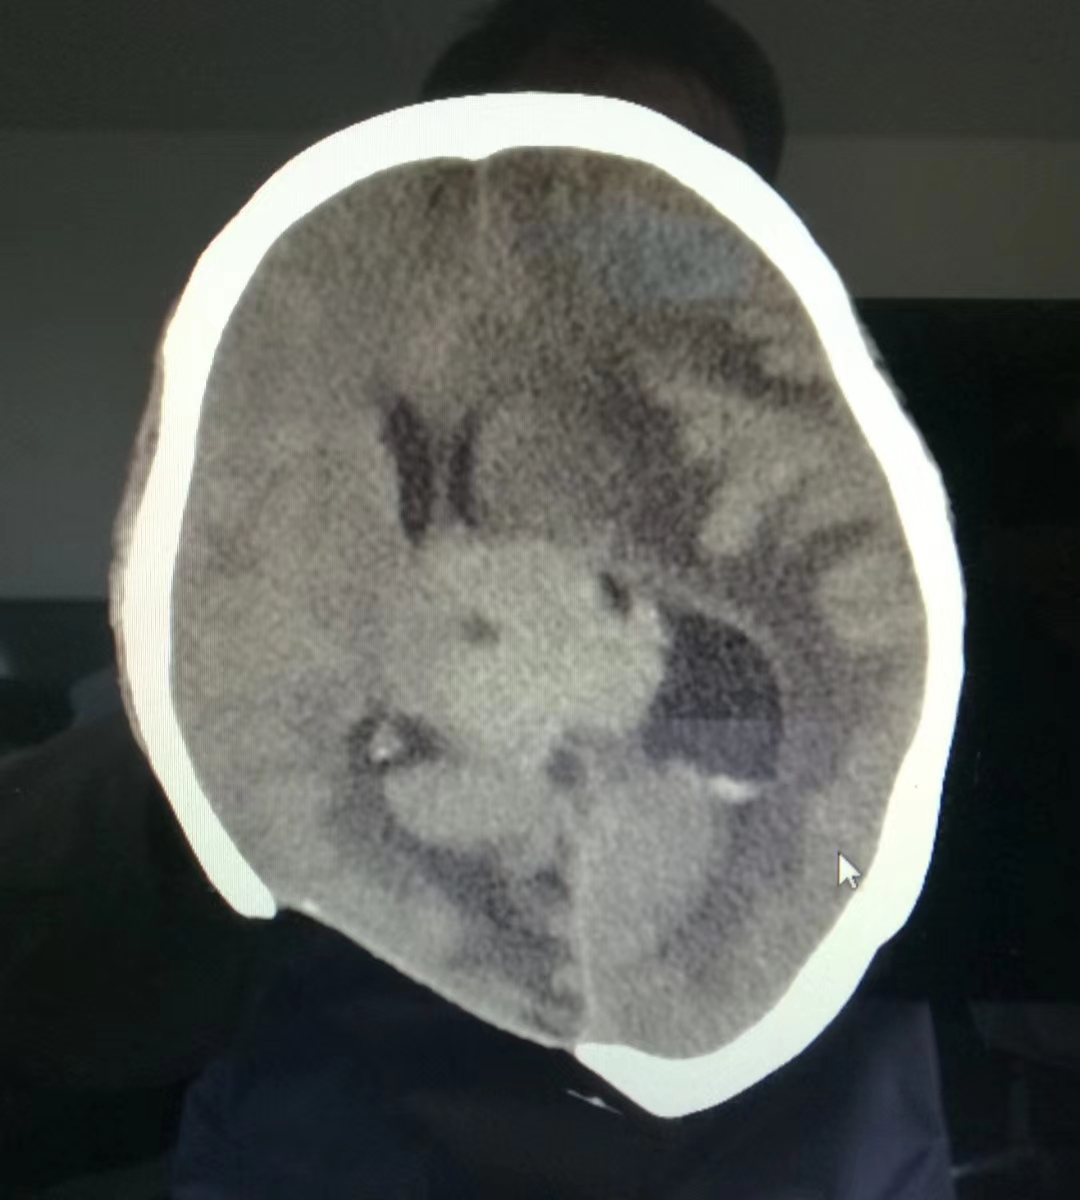

术前CT